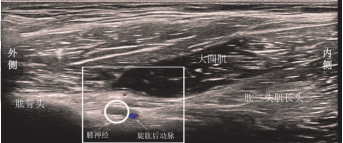

AN後路超聲解剖學特點(圖2):

受檢者取坐位,肩膀內旋45°呈直立位,肘部彎曲90°,將手掌放在膝蓋上。高頻線陣超聲探頭平行於肱骨長軸,放置於肩峰後外側下方約2cm處。重要的解剖結構包括肱骨頭、肱骨幹、橫切面的小圓肌、縱切面的三角肌和肱三頭肌。

三角肌、小圓肌和肱三頭肌之間的間隙可見PCHA。AN位於小圓肌、三角肌後部的深處、肱三頭長頭和肱骨幹之間的神經血管間隙中,超聲顯示PCHA短軸聲像及 PCHA上方呈篩網狀的AN短軸聲像。